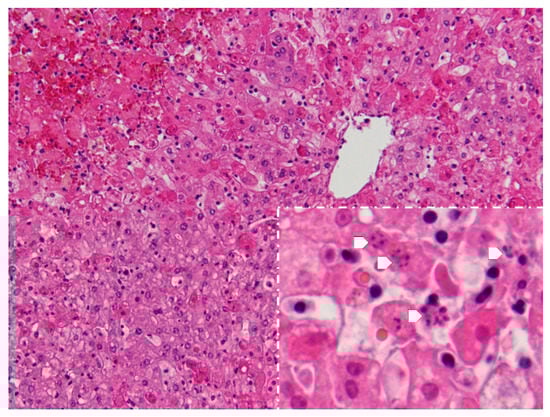

The following microscopic lesions were observed: Liver: severe generalized perilobular haemorrhagic necrosis (Figure 3 and Figure 4). Discrete infiltration by mononucleated inflammatory cells, mainly macrophages and lymphocytes, around portal triads. Fine brown pigment in the cells of the portal bile ducts. Spleen: diffuse necrosis of the entire red pulp revealed by deposition of fibrinoid acidophilic material drawing serpiginous patterns in the parenchyma (Figure 5). The regular presence of lymphoid follicles around central arterioles. Pancreas: interlobular oedema and necrosis of adipocytes, both intralobular and interlobular. No changes were present in the secretory cells. Stomach: no significant changes were observed. Small intestine: Necrotic enteritis, particularly in the duodenum, with loss of villi and deposition of fibrin in the proximal mucosa (Figure 6). Kidneys: the areas of surface retraction in both kidneys corresponded to segmental fibrosis affecting cortex and medulla. In these areas, there was a loss of tubules and glomeruli, which were moderately congested. No microbial agents were identified in any organ and the results of the microbiological analysis were also negative.

Figure 3. Liver. Severe haemorrhagic necrosis consistently affects perilobular areas or acinar zone 1, conspicuous due to the bright red colour close to the portal areas (H&E, 40×).

Figure 4. Liver. Apart from perilobular haemorrhagic necrosis, single-cell necrosis is present in dispersed hepatocytes in acinar zones 2 and 3, which surround the periacinar vein in the upper right. Inset-magnification of the acinar zones 2 and 3, showing various cells with the fragmentation of the nucleus-karyorrhexis (arrows) (H&E, 100×, inset 400×).